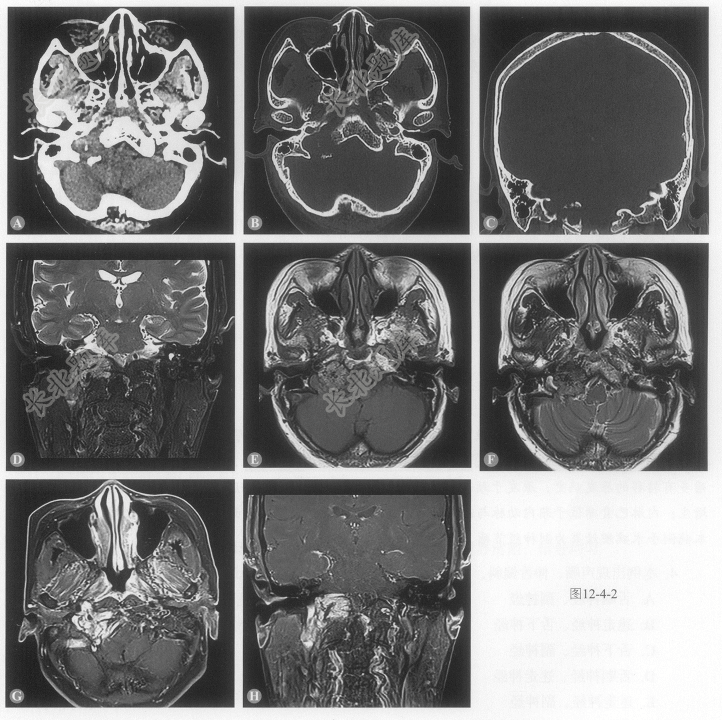

- 多项选择题1.患者的影像学表现包括:

A、病变主体呈不规则形T

WI略高信号,T2WI略高信号影B、病变内见多发点条状血管流空信号影

C、增强呈明显不均匀强化

D、右侧颈静脉孔、舌下神经管受累

E、病变邻近骨质呈虫噬状侵蚀、破坏

- 多项选择题3.本例影像学表现的最可能的诊断:

A、副神经节瘤

B、神经鞘瘤

C、转移瘤

D、脑膜瘤

E、内淋巴囊瘤